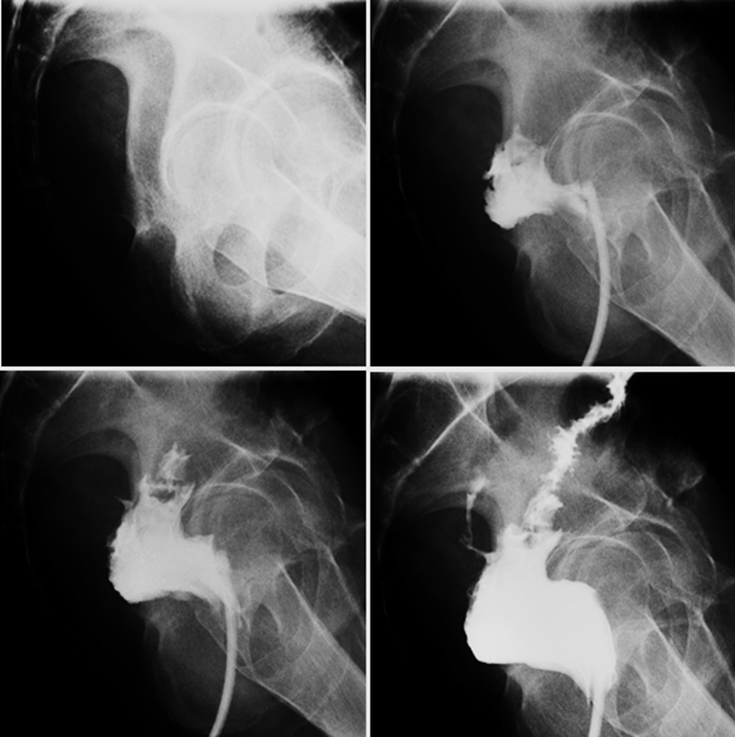

1. A single-contrast water-soluble contrast enema was performed under fluoroscopic guidance.

Explanation: On post-contrast imaging, posterior leakage is observed from the anastomotic suture line.

Fluoroscopy: The colorectal anastomotic suture line is visible posterior to the iliac crest. Following contrast administration, posterior leakage is observed from the anastomotic site into the presacral space. The diameter of the leaking tract is approximately 3 mm. In addition, incomplete distension of the proximal colon suggests the presence of inflammation.

Imaging Features

On fluoroscopic examination, extravasation of contrast material from the anastomotic site is observed. On CT, associated findings may include pneumoperitoneum and extraluminal fluid collections.